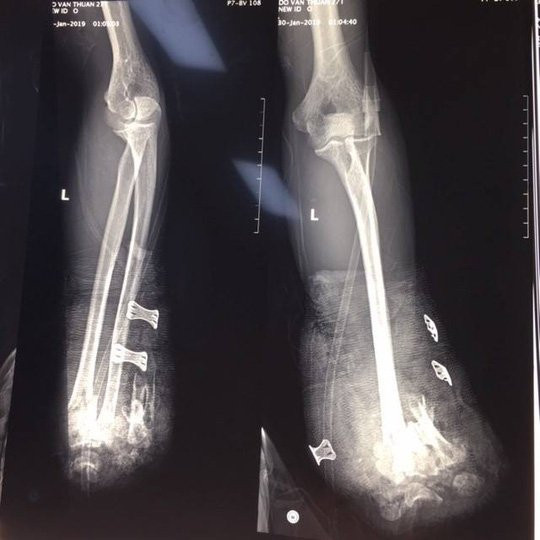

Hình ảnh X quang cho thấy nạn nhân bị dập nát 1/3 dưới 2 xương cẳng tay - Ảnh: Bệnh viện cung cấp

Tại bệnh viện, bệnh nhân đã được mổ cấp cứu cắt cụt để ngỏ 1/3 giữa cẳng tay phải, cắt lọc cơ dập nát cẳng tay trái, kết xương hàm dưới, sau mổ phải điều trị tiếp tại khoa Hồi sức tích cực của bệnh viện. Hiện tình trạng bệnh nhân đã giữ được tính mạng, tuy nhiên sẽ để lại di chứng nặng nề.